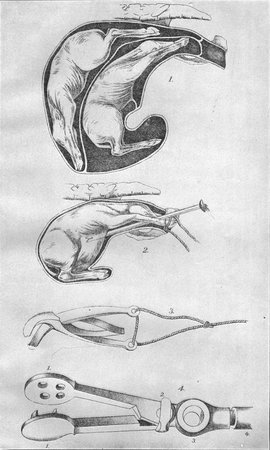

| Plate I. Position of the first stomach (rumen or paunch) | 48 |

| II. Stomachs of ruminants | 48 |

| III. Instruments used in treating diseases of digestive organs | 48 |

In some cases the foreign body, either because it is in the chest portion of the esophagus, and so beyond reach, or because too firmly seated, can not be dislodged from the neck by pressing and manipulating that part externally. In such event we must resort to the use of the probang. (Pl. III, figs. 2 and 3.) A probang is a flexible instrument and adapts itself to the natural curvature of the gullet, and if used cautiously there is not much risk of injury. Before passing the probang, a gag which has an aperture at each end, from which straps pass to be buckled at the back of the head below the horns, is introduced into the mouth. (Pl. III, fig. 4.) The probang should then be oiled, and, the head and neck being held in a straight line by two assistants, the tongue must be partly drawn out of the mouth, the probang cautiously passed along the roof of the mouth into the pharynx and thence into the gullet, through which it is passed down. If resistance is met, gentle and continuous pressure must be used, under the influence of which the object will generally in a short time pass into the stomach. One must be careful not to pass the probang into the larynx and thence into the windpipe, as an animal may readily be killed in this way. This accident is indicated by efforts to cough and by violently disturbed breathing. If such symptoms arise the probang must be withdrawn at once. To [Pg 22] avoid a wrong passage, the end of the tube should be pressed very slowly through the throat until its presence in the esophagus is assured. After it is once in the esophagus care is still necessary, because the walls of this tube may easily be torn.

In urgent cases the gas must be allowed to escape without delay, and this is best accomplished by the use of the trocar. The trocar is a sharp-pointed instrument incased in a cannula or sheath, which leaves the sharp point of the trocar free. (See Pl. III, figs. 5a and 5b.) In selecting the point for using the trocar a spot on the left side equally distant from the last rib, the hip bone, and the transverse processes of the lumbar vertebræ must be chosen. Here an incision about three-fourths of an inch long should be made with a knife through the skin, and then the sharp point of the trocar, being directed downward, inward, and slightly forward, is thrust into the paunch. (Pl. I.) The cannula or sheath of the trocar should be left in the paunch so long as any gas continues to issue from it. If the cannula is removed while gas is still forming in the paunch and the left flank becomes considerably swollen, it may be necessary to insert it again. It is well, accordingly, to observe the cannula closely, and if gas is found to be issuing from it it should not be removed. When gas issues from it in c onsiderable quantities the sound accompanying its escape renders the exact condition obvious. It is occasionally necessary to keep the cannula in the stomach for several hours. When this is necessary a piece of stout cord should be passed round the neck of the cannula immediately below the projecting rim and then be passed round the animal's body and tied in a secure knot, and a careful attendant must remain with the cow during the entire period that the instrument is in place. The rim surrounding the mouth of the cannula should be in contact with the skin. Whenever the person in charge of the cow is convinced that gas has ceased to issue from the cannula the instrument should be removed.